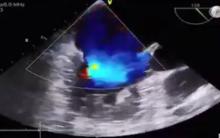

Surgical Correction of Barlow's Mitral Valve [1]

Steven Livesey of Southampton General Hospital, Southampton, UK, discusses the anatomy of Barlow's mitral valve and the options for correction. Dr. Livesey demonstrates his repair technique with an operative video.